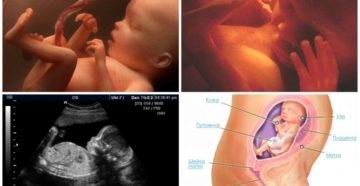

23 неделя беременности На 23 неделе беременности будущая мама постоянно прислушивается к малышу, его шевелению….